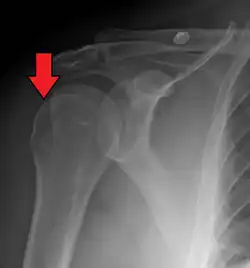

Anterior shoulder dislocation on X-ray with a large Hill–Sachs lesion

A Hill–Sachs lesion, or Hill–Sachs fracture, is a cortical depression in the posterolateral head of the humerus. It results from forceful impaction of the humeral head against the anteroinferior glenoid rim when the shoulder is dislocated anteriorly.